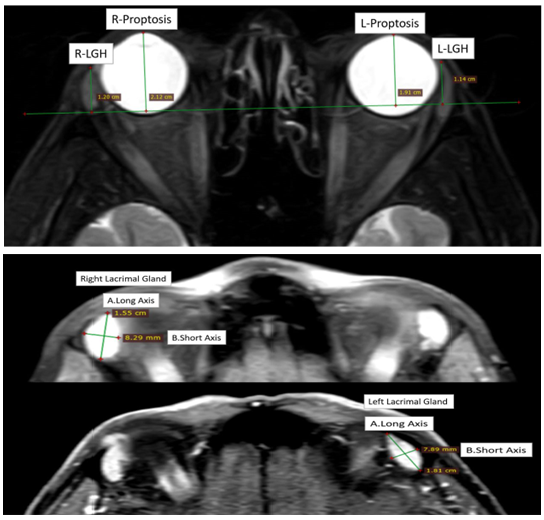

Lacrimal Gland Measurements in Patients with Graves’ Ophthalmopathy

Elmas Yuksel, MD, Abdullah Sukun, MD